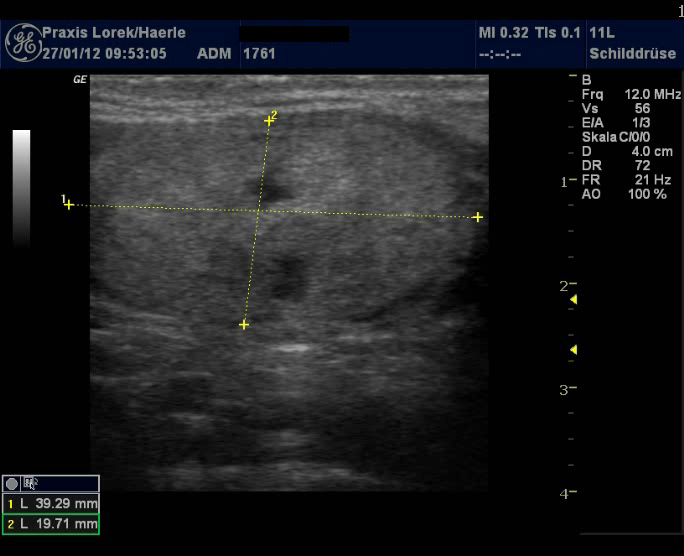

| Abb. 3 und 4:

Ungleichmäßige Echoarmut der Schilddrüse bei einer

27-jährigen Patientin, Schilddrüse mit etwa 19,4 ml leicht

vergrößert, eher hypertrophe Verlaufsform (klassische

Hashimoto-Thyreoiditis), Patientin klagte unter Müdigkeit während

ihrer ersten Schwangerschaft 2005. Pseudoknoten Tirads 3 im linken dorsalen

Lappen. |